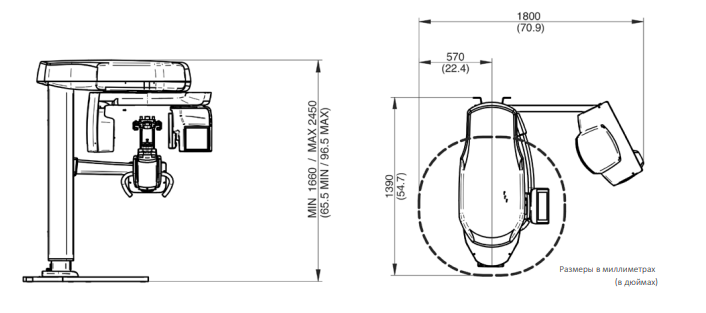

NewTom GiANO HR новейшая модель была официально представлена на международном конгрессе радиологов ECR 2018 в марте в Вене. Благодаря обновленным системам механики и запатентованным механизмам работы аппарат отличается от своих сверстников Высочайшим качеством получаемых изображений, как 2D, так и 3D. Лучшее качество снимков и мы отвечаем за это! Этот аппарат заменит три аппарата! Панорамный аппарат, цефалометрическая приставка и конусно-лучевая компьютерная томография интегрированы в единую платформу. В комплекте детектор для выполнения 3D исследований с захватом области 13х16 см, Сьемный 2D CMOS детектор для выполнения панорамных исследований, и ТРГ.

- Крепление аппарата к стене